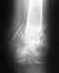

Re: Перелом левой пяточной кости

Чем обусловлены разные взгляды - это слишком много рассказывать. Действительно, при таком положении фрагментов шансы, что все будет приемлемо, высокие. КТ надо сделать на всякий случай.